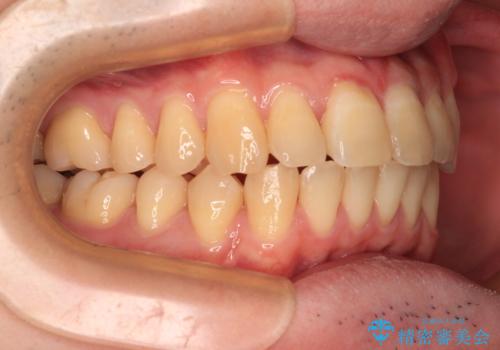

【モニター】前歯のデコボコとクロスバイト ワイヤー矯正で短期間に仕上げる

- 前歯のデコボコとクロスバイトを気にして来院された患者様です。